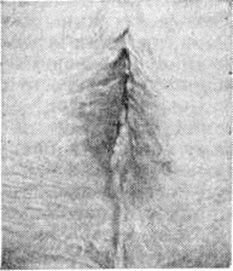

Крауроз вульвы

При осмотре кожа наружных половых органов истончена, сморщена; большие половые губы плоские, лишены волос; малые половые губы и клитор сглажены или отсутствуют, вход во влагалище сужен (рис.).